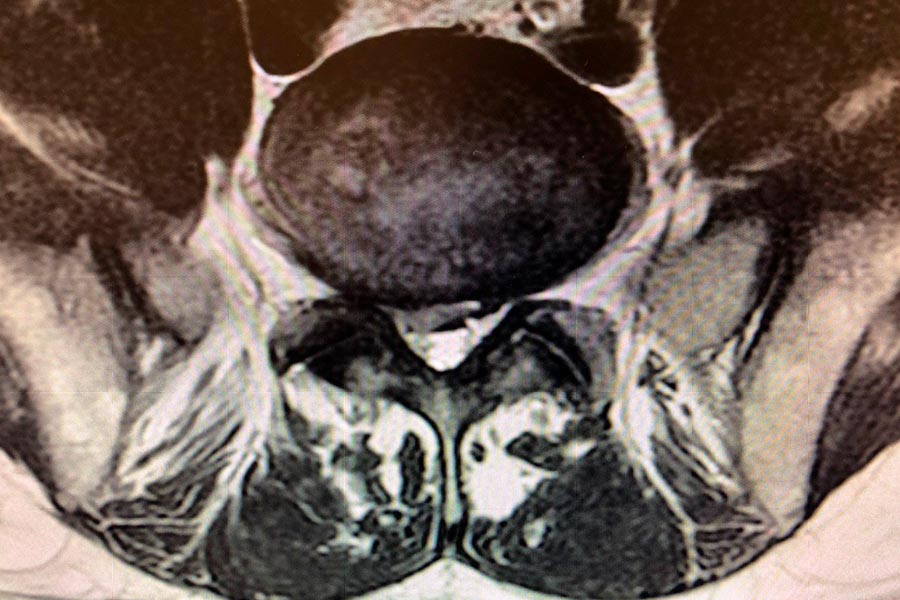

Caso clínico de Hernia en el disco L5S1 lateralizada

Hernia discal lateralizada

En este caso, el Doctor Elgeadi se encarga del tratamiento, con una tecnica de cirugía mínimamente invasiva, de localizar y extraer una hernia discal, de pequeño tamaño en la L5S1.

A pesar de que el tamaño de la hernia es bastante pequeño, el paciente sufre molestias en el tren inferior, con dificultades a la hora de caminar o hacer esfuerzos con las piernas.

hernia-discal-l5si-lateralizada